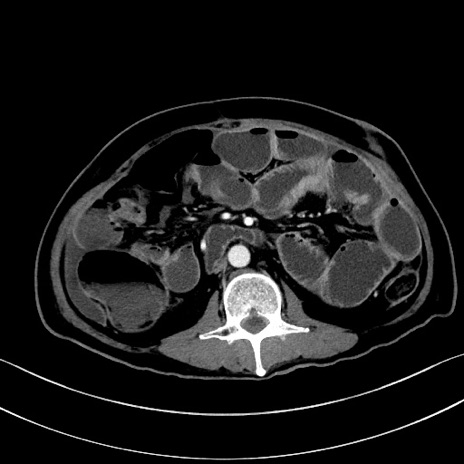

症例28(横断像)

【症例】60歳代男性

【主訴】嘔吐

【現病歴】胃癌にて胃全摘後。食思不振が悪化し、夜中に嘔吐することがある。

【既往歴】胃癌、胃全摘、脾摘、胆摘後

【データ】WBC 5900、CRP 10.56